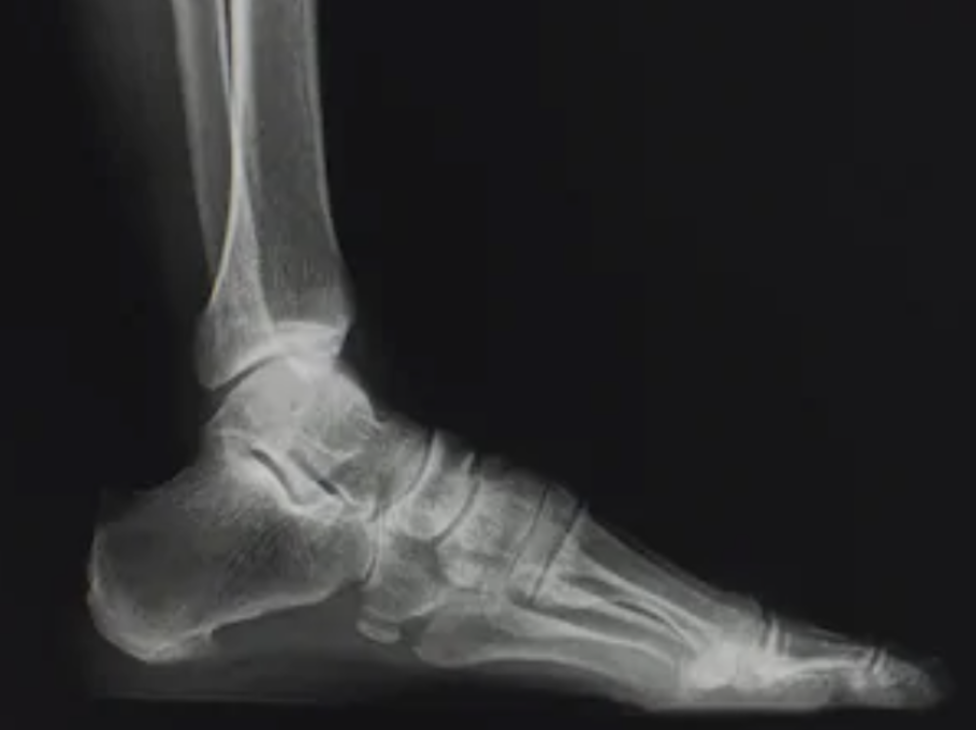

Q

What view is this?

A

Lateral View